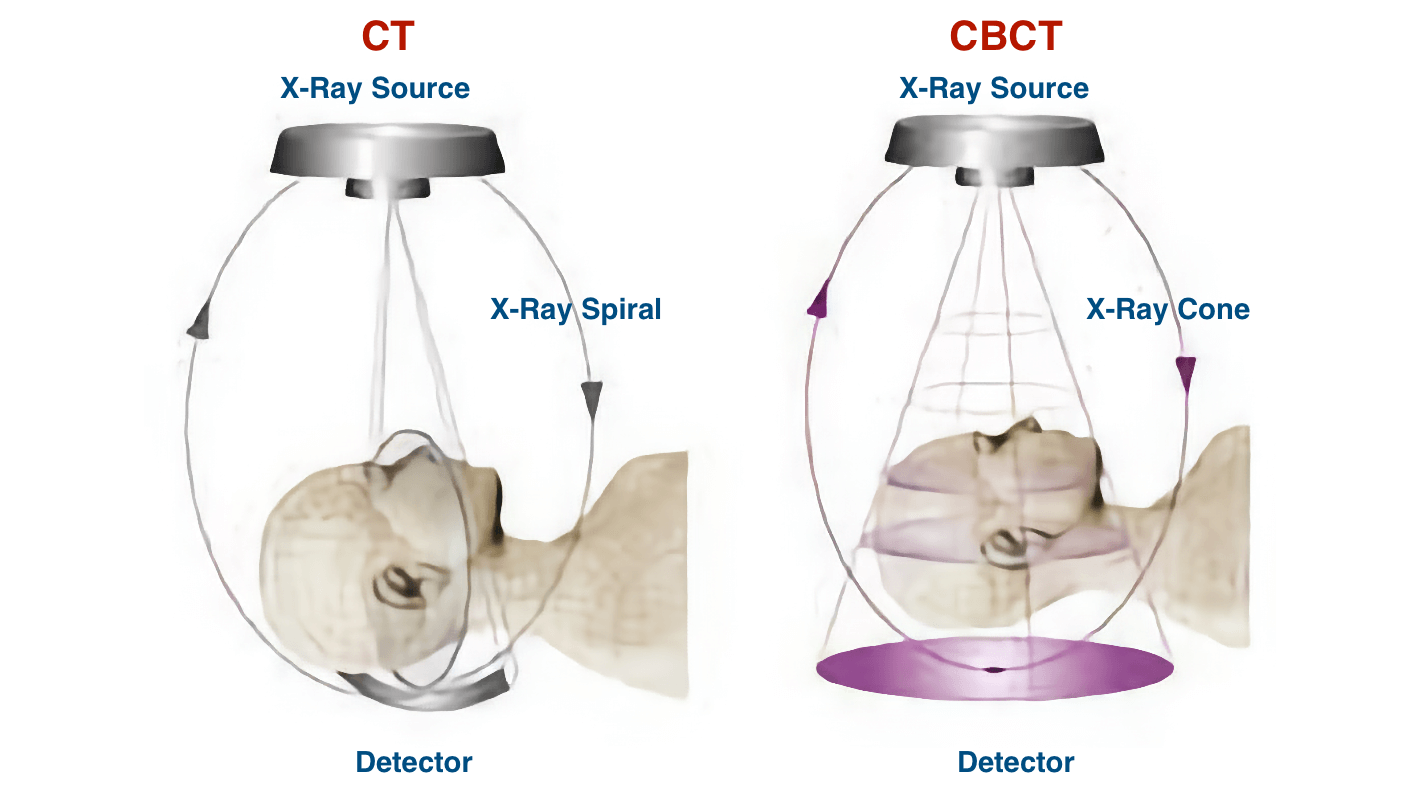

What is the difference between computed tomography (CT) and cone-beam computed tomography (CBCT)?

CT technology was developed in 1967 by Sir Godfrey Hounsfield and is based on capturing images on the detector screens in multiple planes until a complete image is obtained. This technique exposes the patient to more radiation. The images obtained are useful in maxillofacial trauma, growth and development studies, oral and salivary gland pathology and dental implant planning.

In contrast to CT imaging, in CBCT (Cone Beam Computed Tomography) imaging, the three-dimensional volume of the data is obtained in a single scanner sweep in which the 2D sensor and the radiation source rotate synchronously around the patient's head by 180º or 360º depending on the CBCT equipment used.

In addition, in a CBCT system, the X-ray beam is a conical shape and produces a cylindrical or spherical data volume, known as the FOV (field of view). The size of the FOV differs between scanners, with some capable of capturing the entire maxillofacial skeleton. Also some CBCT machines can adjust the height of the cylindrical FOV to capture a single area, which reduces the radiation dose to the patient.